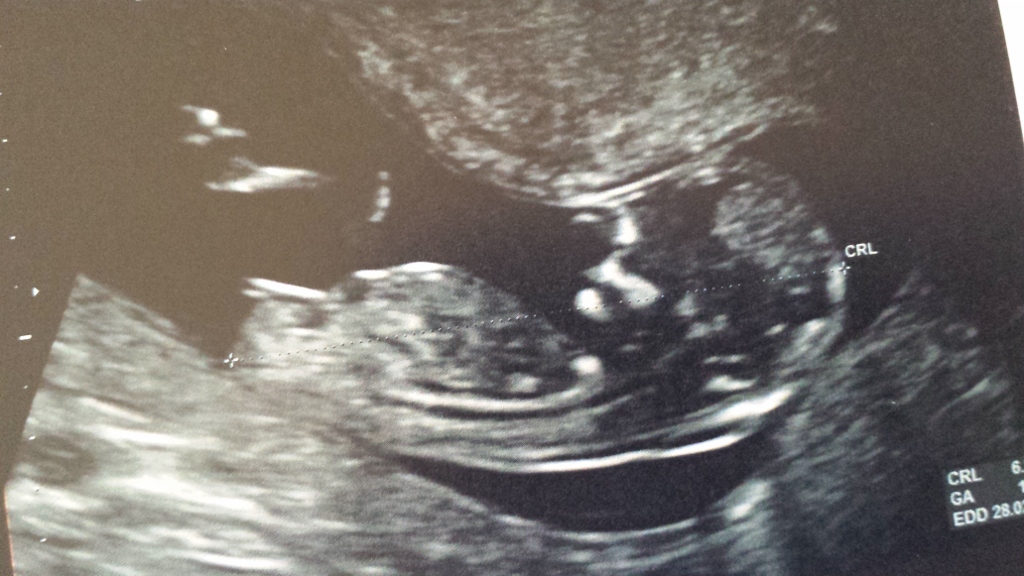

16 weeks 6 days potty shot

Attachment 14224